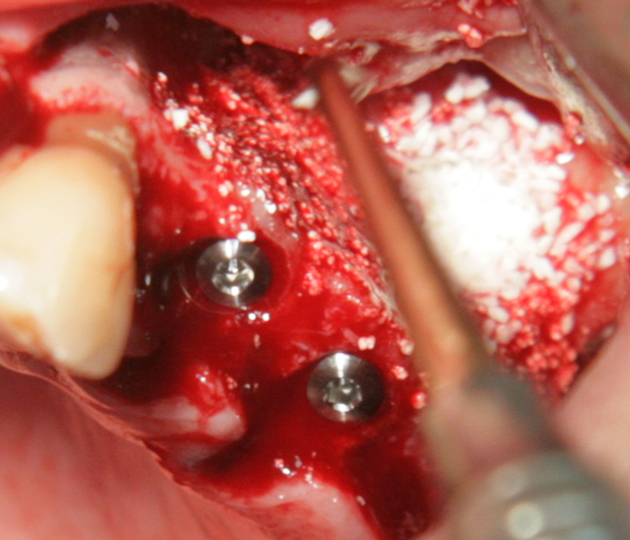

Отворен максиларен синус в началото на интервенцията. Случаят е интересен със следното - твърде атипична форма на трепанационния отвор. На какво се дължи на това - на лошо планиране на оперативния достъп или на нещо друго? Дължи се на факта, че отначало въпросната намеса беше планирана като балонен синуслифт; за съжаление обаче мембраната на синуса се разкъса и надуването на балона стана невъзможно.